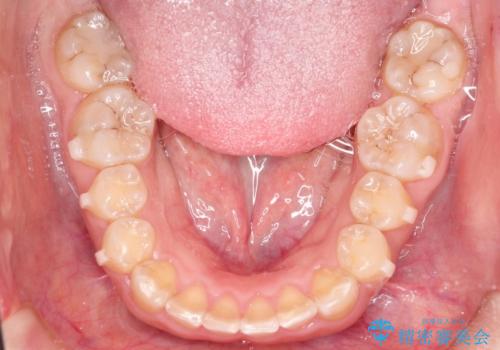

抜歯は行わず上顎の奥のスペースを利用して歯をスライドする方法の他に歯列弓の拡大やディスキング(歯と歯の間の隙間を作る処置)を行い叢生を改善しました。

奥歯を後ろに送る工程では上下でゴムかけをしていただきました。

見た目、嚙み合わせ及び、治療期間や施術内容に大変ご満足いただきました。